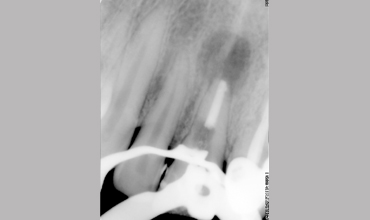

Management Of Internal Root Resorption In Maxillary Central Incisor Pre-operative Radiograph Removal Of Granulation Tissue With Ultra

Management Of Internal Root Resorption In Maxillary Central Incisor